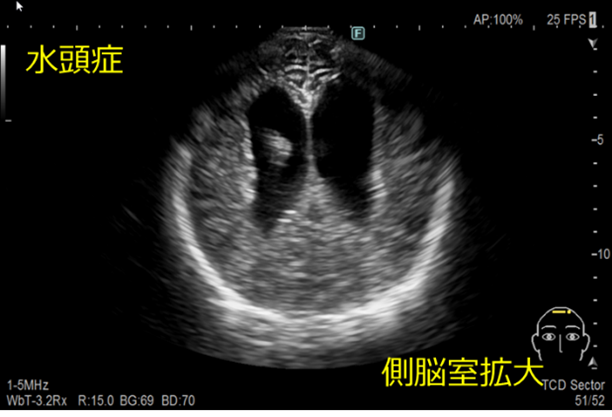

経頭蓋超音波検査

頭蓋骨早期癒合症の有無、頭蓋内の病変の有無や性状などについて観察しています。

水頭症とは

髄液が頭蓋内腔に過剰に貯留した状態のことです。

脳室拡大、頭蓋内圧亢進、脳実質の圧迫などが見られます。